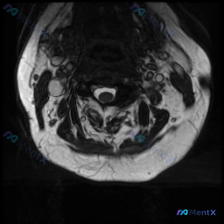

看到这张颈椎MRI,分享一下我的读片思路,这个病例其实挺容易踩坑的。 一、影像基本信息 这是一张颈椎MRI T2加权轴位图像,层面在颈椎中下段,可以看到椎体、椎管、脊髓、椎间盘和周围颈部软组织,解剖结构显示清晰: - 中央可见圆形脊髓,周围是高信号脑脊液 - 能看到椎体、椎板和后方肌肉群,前方可见喉...

看到一个挺有临床意义的病例,整理了一下影像和分析思路分享给大家。 病例核心信息 这是一份颈椎下段(C5-C7水平)MRI T2加权轴位影像,用户临床提示怀疑椎间盘病变,我们先来整理影像所见: 1. 椎管与脊髓:脊髓形态信号正常,无受压变形、局灶异常信号,蛛网膜下腔间隙清晰无狭窄 2. 椎体与椎间盘:...

看到一个很有代表性的读片问题:临床怀疑颈椎间盘病变,提供了单张颈椎MRI T2加权轴位图像,整理一下完整的分析思路跟大家分享。 一、影像基本信息 这是一张颈椎MRI T2加权轴位图像,脑脊液呈高信号、脊髓呈中等信号,解剖定位为颈椎间盘水平层面。 二、系统读片结果 我按规范顺序梳理了所有结构: 1....